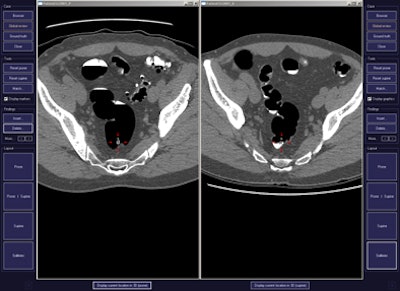

CAD first-reader gallery evaluation shown in a screening patient with a 10-mm tubular adenoma in the rectum. Above (left monitor), all 15 CAD markers in a volume are presented to the reader, line by line, as a collection of CT image galleries. They are sorted top to bottom by decreasing level of confidence, as computed by the CAD algorithm both for the prone (shown) or for the supine (not shown) position. CAD finding P:1 (first row of images) displays the polyp (crosshair) in all six gallery images. Note that the typical imaging characteristics of a polyp are already recognizable within the gallery images. The remaining CAD findings P:2-P:5 (image rows 2-5) display false-positive detections in the stomach (P:2), on the residual fluid layer (P:3), in the stomach (P:4), and in the terminal ileum. CAD findings P:6-P:15 are not shown. Below (right monitor), standard axial and optional coronal and sagittal 2D images (not shown). Optional 3D target views (not shown) of prone and supine datasets are used, first, to further evaluate potential polyp candidates or CAD findings on complex structures and, second, to perform a complete 2D review of the prone and the supine CTC datasets. The 2D axial prone and supine CT images show the polyp (crosshair) marked by CAD (marker 1) in both positions. All images courtesy of Dr. Thomas Mang.